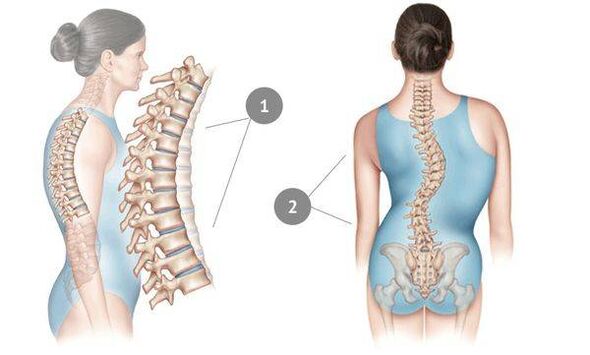

Thoracic osteochondrosis is a disease that usually appears in adults and does not fully manifest itself for a long time.This is due to the fact that the thoracic spine is naturally supported and fixed by the ribs - therefore, the intervertebral discs provide good protection.

In this disease, the core of the spinal disc becomes thinner and dries out, the fibrous tissue around it begins to deteriorate, and the cartilage tissue undergoes negative changes.The spine becomes able to cope with normal loads - and this is mainly expressed in the appearance of pain, which is vaguely expressed at first, but becomes more and more intense over time.However, with significant stress - sedentary lifestyle, sedentary work, constant stress, bad posture and back injuries - sooner or later osteochondrosis affects the chest region.The disease is considered very common - every third adult suffers from it.

Osteochondrosis of the spine is expressed in scoliosis;sometimes the disease spreads to the cervical vertebrae and causes loss of voice.

Almost all of the listed methods are not aimed at eliminating osteochondrosis as such, but at relieving inflammation and reducing the intensity of pain.The main goal of treatment for breast osteochondrosis is to eliminate pain.At the same time, manual therapy and exercise therapy can "straighten" the spine, increasing the distance between the vertebrae and preventing compression.However, it is the duty of the patient to perform therapeutic exercises regularly - otherwise it will not give any result.